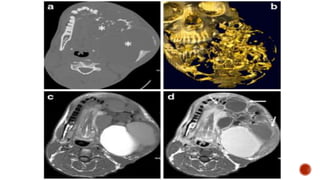

 Neurogenic bladder

 Scout film shows enlarged renal shadows

 Full bladder image shows a well distended urinary bladder with multiple broad

based diverticulae and wall irregularities.

 On straining there is no vesicoureteric reflux.

 Trauma

 Multiple sclerosis

 Parkinson disease

 Cauda equina syndrome

 Neuritis

 Sensory : Inability to sense bladder fullness results in a large rounded and smooth

bladder. Voiding is often preserved.

 Motor : Atonic large bladder with the inability of detrusor contraction during

voiding.

 Reflex/uninhibited : Lesions above S2 level (Christmas tree/pine cone appearance)

 Self catheterization

 Prevent complications

 Bladder training

 Cystoplasty

 Neuromodulation

 Non-neurogenic neurogenic bladder

 Neuropsychological entity

 Associated with voiding dysfunction, UTI, incontinence.

 The latter can exacerbate the former leading to a vicious cycle

 large bladder capacity

 reduced sensation

 increased maximal urethral closure pressure

 detrusor underactivity.

 Several hypotheses:

 hormonal changes (PCOS)

 abnormal stabilization of the muscle membrane

 primary failure of relaxation of the striated muscle of the urethra sphincter

 increased urethral afferent activity, inhibiting the bladder afferent signals from reaching the

brain by potentiating a spinal mechanism of urinary continence.